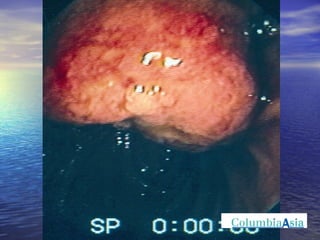

ERCP (Endoscopic Retrograde Cholangio Pancreatography) is an endoscopic procedure used to diagnose and treat issues in the bile and pancreatic ducts. It involves positioning an endoscope and using x-rays to view the ducts while performing procedures like draining bile ducts, removing gallstones, and placing stents. Potential complications include pancreatitis, bleeding, infection, or perforation. Careful pre- and post-procedure steps like monitoring and antibiotics are important to minimize risks.